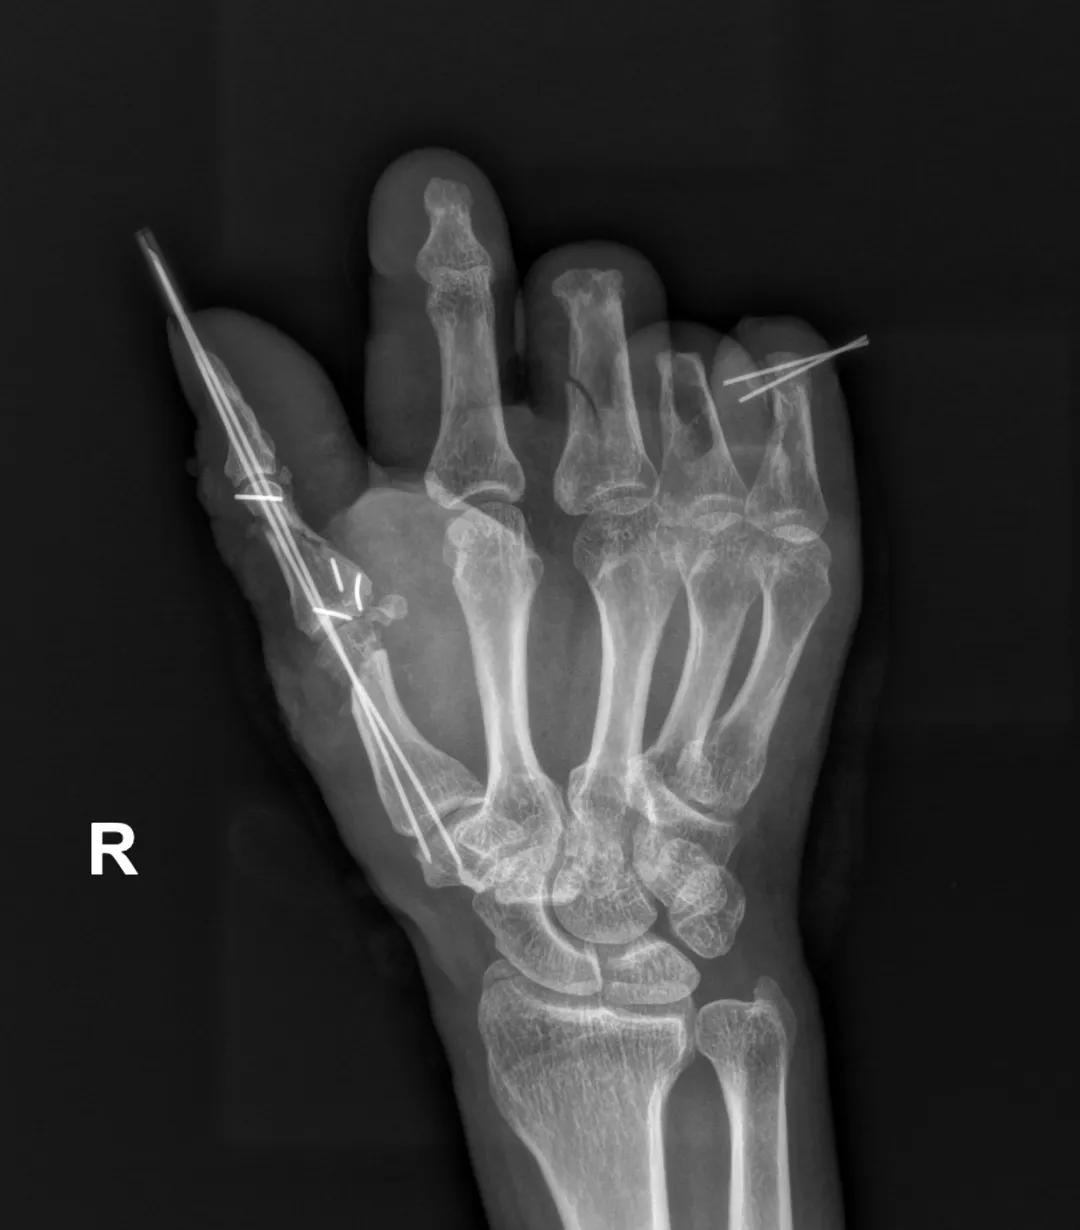

术后X光片显示接好的手